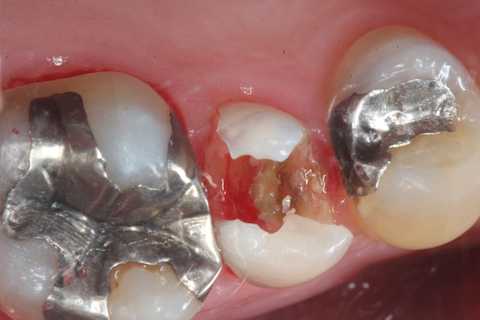

今日の充填治療55(遠心隣接面カリエス) 2023.12.21